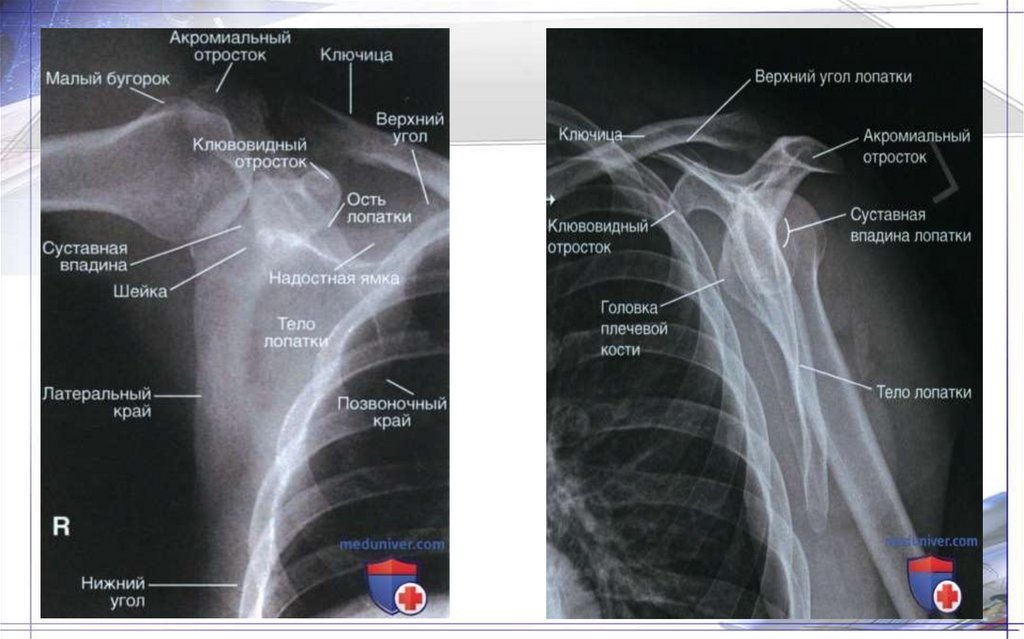

36. Плечевая кость(Humtrus)